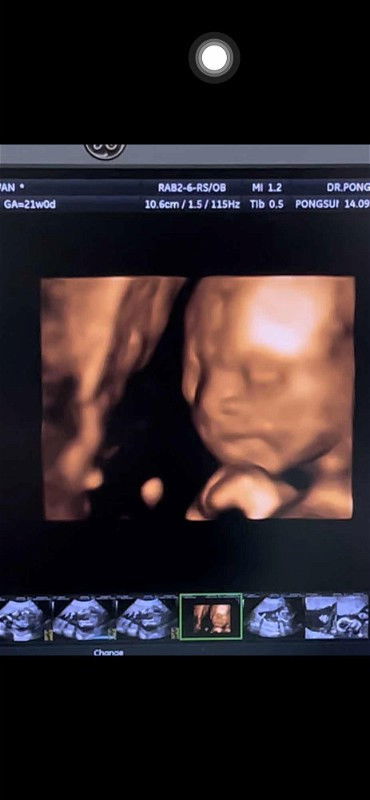

U/S ตอน 13w ก่อนตรวจ NIPT หมอเดาว่าเพศหญิง แม่ดีใจสุดๆ เพราะลูกคนแรกเป็น ผช แล้ว ตอนนี้ 14w .. ผลออกอิแม่ได้ลูกชาย 100%😂 ผลเสี่ยงต่ำ ทุกอย่างปกติ .. ตั้งแต่รู้ว่าท้อง แม่ไม่แพ้เลย มีอ้วกแค่ 1 วัน และตอน 7-11w แม่แท้งคุกคาม มีเลือดออก ต้องฉีดยากันแท้งทุกอาทิตย์ แต่น้องเกาะแม่แน่นมาก แข็งแรงสุดๆ แล้วก็กินทุกอย่างได้ปกติ ไม่ได้ชอบอะไรเป็นพิเศษ แต่ชอบกินเผ็ดๆ แต่ถึงยังไงแม่ก็รักหนูค่ะ ปิดอู่ค่ะเพราะแม่อายุ 40 ปีแล้ว 😂 #กำหนดคลอด25มกราคม67 #ทีมมกรา67